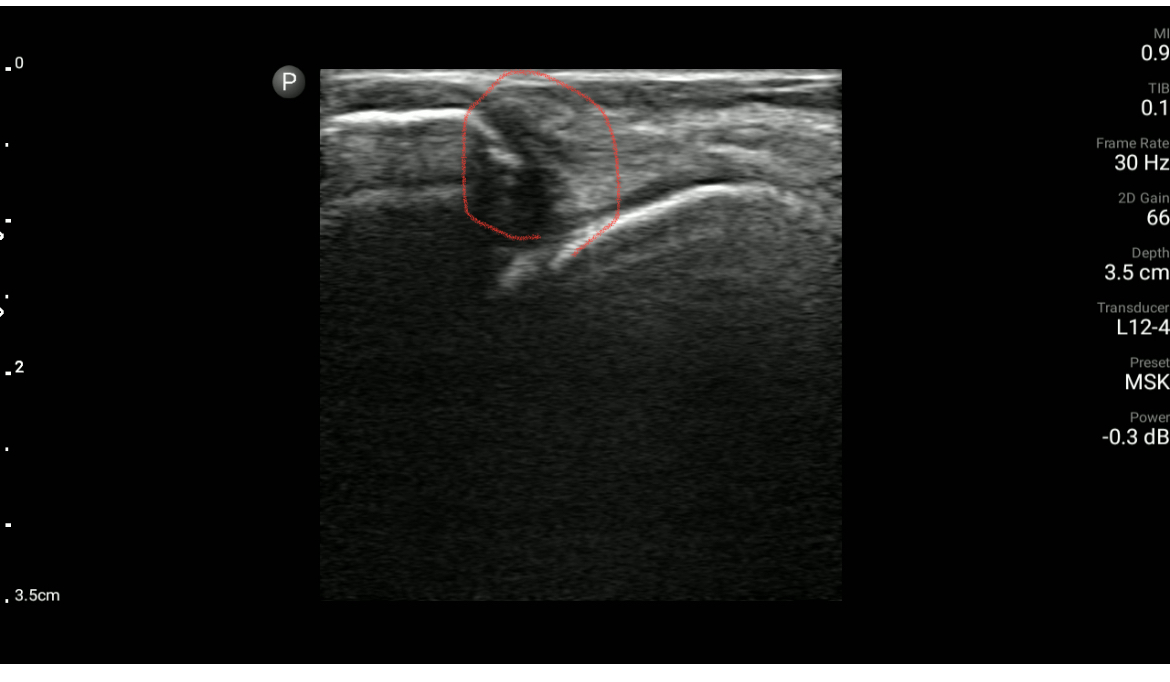

エコーでもいいので状態を把握しなければ治療フェーズの判断が難しい。熱感・腫脹など体表から見てとれるものもありますが

靭帯単独損傷と混同しやすいので、圧痛部位・腫脹の広がりを確認